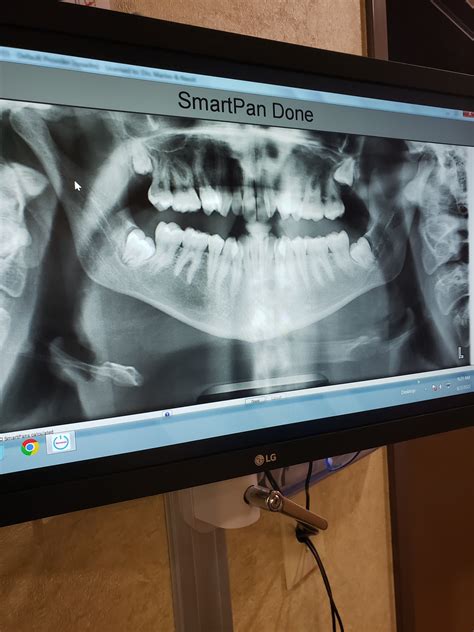

Panoramic Full scene of the mouth. Entire jaw, all dentition, and sinus areas.

Undergo a sapience tooth Xray is a straightforward and speedy operation. You will typically be enquire to stand in a specialised machine or sit in a dental president while the technician view the equipment. For a bird's-eye X-ray, you might sting down on a small plastic tab while the machine revolve around your caput. This operation is whole painless and direct less than a second to complete.

ℹ️ Note: Always ask your dentist to prove you the images on the monitor. Find the position of your own tooth can make the necessity of a procedure much easygoing to translate.